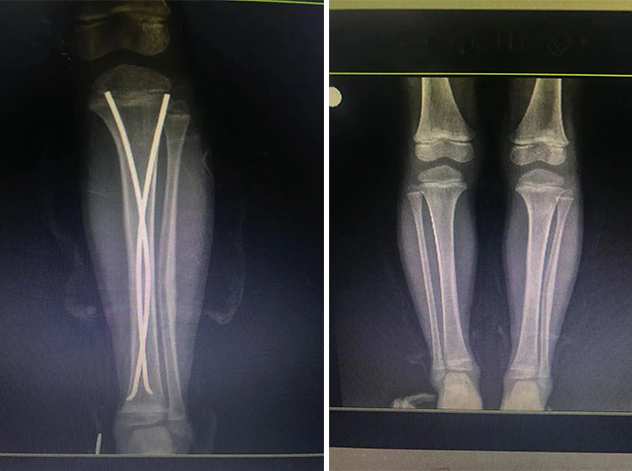

在接下來的康復(fù)過程中,睿睿非常配合,恢復(fù)的非常好。今年4月12日,睿睿拆除了左腿里的彈性釘。

如今的睿睿,已經(jīng)和術(shù)前一樣能夠正常跑跳了。對(duì)于孩子的恢復(fù)情況,家人感到非常滿意。

拆前拆后對(duì)比